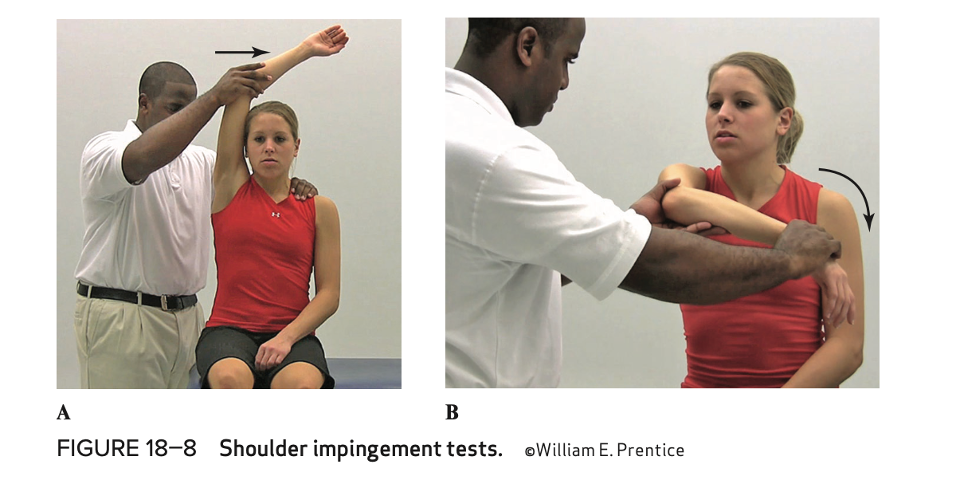

Shoulder impingement test (purpose, how, positive sign )

purpose - impingement of soft tissues

how - horizontal adduction and forced internal rotation, forced flexion and adduction overhead

positive sign - pain/facial grimace on movement